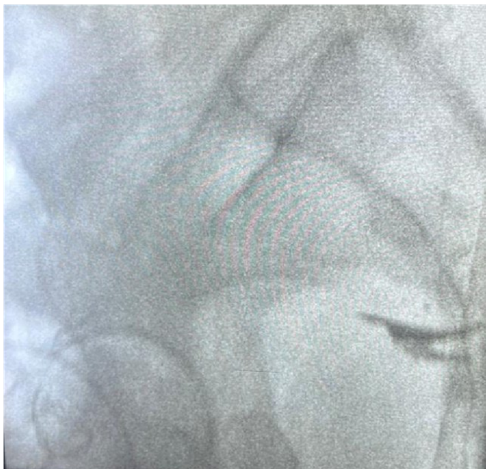

Diagnostic workup started with a pelvic ultrasound, which was unremarkable, followed by a pelvic CT scan revealing metallic-density material near the bladder dome causing significant artifact. This material extended posteriorly in contact with the sacral bone (at the S3-S4 junction) outside the sacral foramina, with bone lysis surrounded by osteosclerotic reaction.

Figure 1: Pelvic CT scan showing an endopelvic gossypiboma